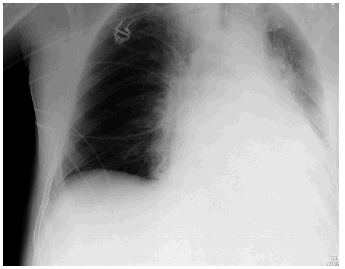

Paciente de 72 años de edad ingresado en Unidad de Cuidados Intensivos (UCI) con insuficiencia respiratoria global por una reagudización de enfermedad pulmonar obstructiva (EPOC). El paciente tiene dificultades para la desconexión de la ventilación mecánica por atelectasias de repetición y acidosis respiratoria grave. En la figura 1 se observa la radiografía de tórax en ventilación mecánica y en la figura 2 una de la imágenes de atelectasia al reducir el soporte ventilatorio. Se realizó electromiograma de diafragma mediante punción del pilar anterior por acceso retroesternal, en el que aparecieron datos de denervación (fibrilaciones y ondas rítmicas de denervación "marcadas con un circulo rojo") (fig. 3). El paciente fue dado de alta de UCI y del hospital con soporte ventilatorio parcial.

Figura 2.